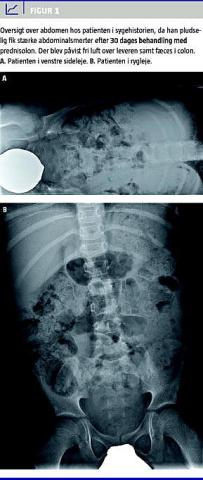

Efter 30 dages prednisolonbehandling blev patienten genindlagt med stærke smerter i venstre side af abdomen. Objektivt var han smerteforpint, bleg, cushingoid og afebril. Abdomen var opdrevet, ømt og spændt. Ved OOA sås der fri luft over leveren (Figur 1 ). Ved eksplorativ laparotomi blev der påvist et 2 × 2 mm stort perforeret ulcus højt på corpus af ventriklens forflade. Ulcus blev oversyet med omentsnip, og der blev behandlet med antibiotika i ti døgn og med omeprazol, indtil prednisolon blev seponeret i henhold til vejledning [3]. Antigen for Helicobacter pylori i fæces var negativ. Det postoperative forløb var ukompliceret. Efter fire måneder blev det vha. UL påvist, at leveren var normaliseret, og levertallene var normale. Patienten blev ikke behandlet med nonsteroide antiinflammatoriske stoffer.

I den kliniske hverdag er det er vigtigt at have mistanke om gastroduodenalt ulcus ved abdominale symptomer hos børn, der er i behandling med systemisk steroid. De hyppigste fund og symptomer hos børn med ulcus er epigastrisk ømhed, natlige mavesmerter, hæmatemese, melæna og vægtstagnation [4]. Ved perforeret ulcus blev der i en større undersøgelse påvist peritonalt abdomen hos 94%, og ved OOA blev der påvist subdiafragmatisk fri luft hos 83% [1].